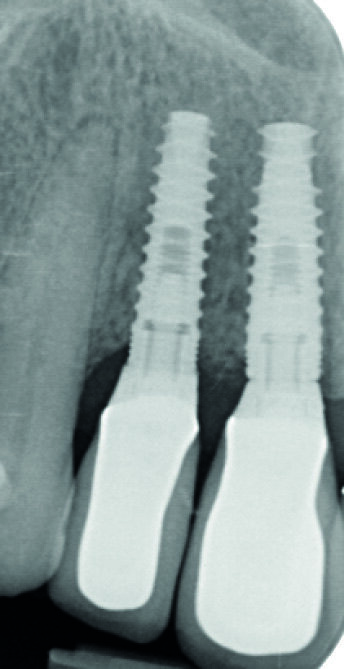

Me M. Ler, âgée de 71 ans lors de la chirurgie, ne présente pas d’antécédents médicaux particuliers, à l’exception d’un cholestérol stabilisé avec des statines (Tahor 10). Elle est traitée depuis 2007 pour une parodontite sévère qui est aussi globalement stabilisée cliniquement, radiologiquement et bactériologiquement. Nous avions déjà réalisé un traitement implantaire en 21 (2008) et 23 (2013) (Fig. 2). La patiente souhaite maintenant mettre des implants en 11 et 12 car les mobilités modérées de ces dents commencent à la gêner dans sa vie quotidienne.

Le volume osseux dans ce secteur est bon et ne présente pas d’infection (Fig. 3). Le choix s’oriente vers une implantation par chirurgie guidée avec mise en charge immédiate.

Fig. 2 : Bilan radiologique « long-cône ». Notez la sévérité des pertes d’attache, mais qui sont bien stabilisées depuis 12 ans.

Fig. 3 : Radiographie long cône du secteur à implanter. Notez l’absence d’infection et la bonne intégration de l’implant en 21, posé en 2008.